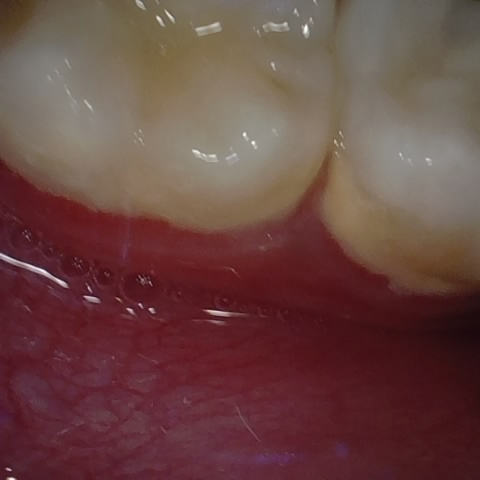

Annotated as "Good"